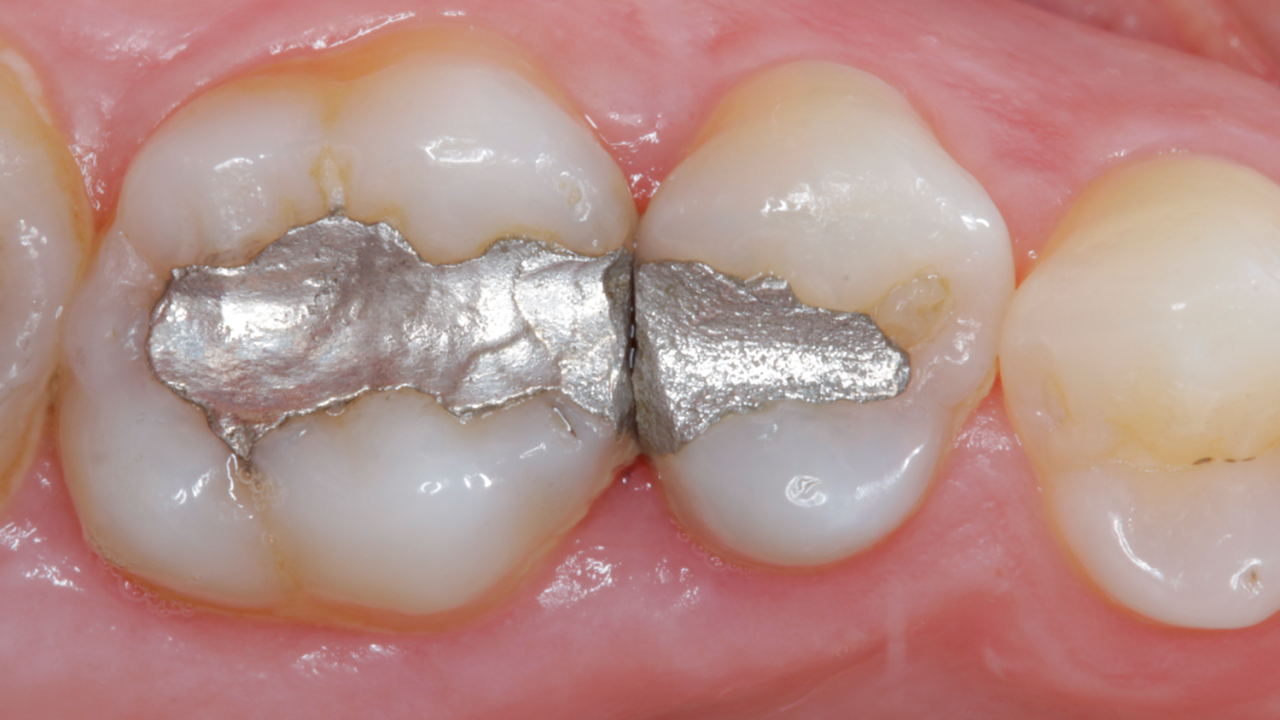

Clinical challenge with advanced layering

Case: Initial case showing defective and leaking old amalgam restorations.

Results: Two-week recall. Final restoration and excellent gloss retention with Ceram.x Spectra ST universal composite A2 and BW giving the tooth back its lost anatomy and natural esthetic appearance.